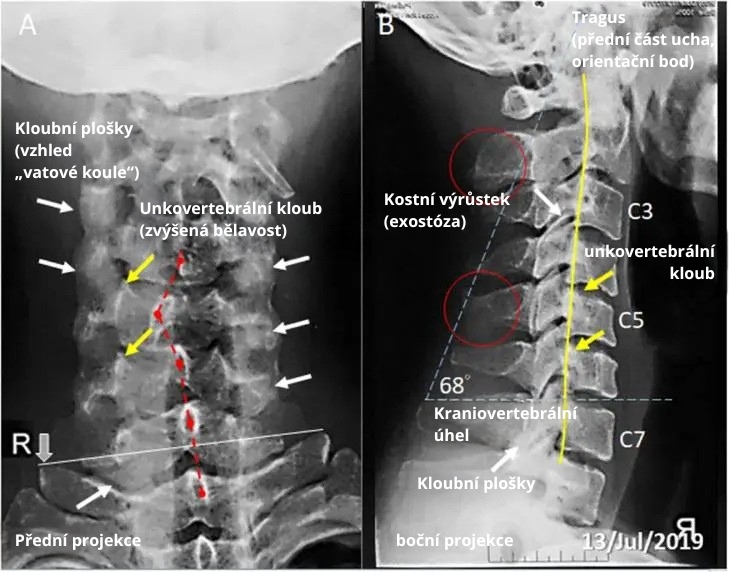

Prípadová štúdia publikovaná v Radiology Case Reports opisuje príbeh 24-ročného YouTubera, ktorý používal svoj smartfón počas dňa minimálne 16 hodín a kontroloval ho každých desať minút. Po takmer roku začal pociťovať pretrvávajúce bolesti hlavy, krku a hornej časti chrbta, vrátane znecitlivenia pravej ruky – typické príznaky syndrómu mobilového krku.

Jeho stav sa zhoršil do tej miery, že nedokázal udržať hlavu vzpriamenú dlhšie ako minútu. Röntgenové vyšetrenie odhalilo abnormálne zakrivenie krčnej chrbtice (žltá čiara), posunuté stavce (červené šípky) a artritické zmeny v krčných kĺboch (biele šípky). Po viac ako troch mesiacoch obmedzovania času pred obrazovkou a cvičení na úpravu držania tela sa jeho ťažkosti výrazne zlepšili.